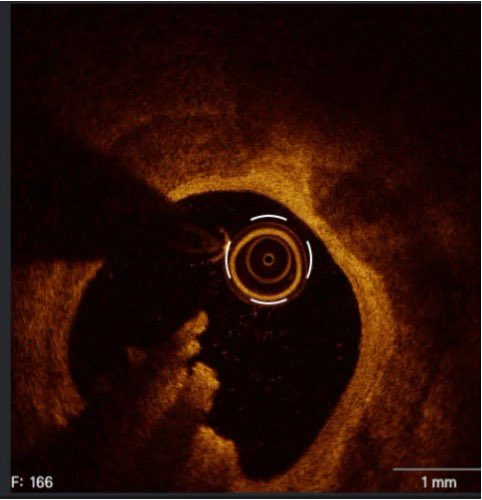

Multi Modality #Watchmanflx

AngioCT for Planning

TEE + ICE + Fluoro for guidance

Perfect result @BSCCardiology @BostonSciLatam @PCRonline @SCAI @TCTMD @SOCiME_ @solaci_online @smexcardiologia